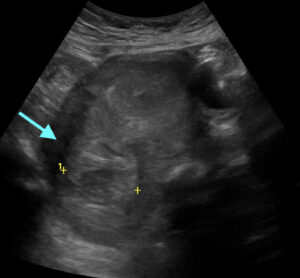

Iatrogenic Uterine Perforation. US Annotated. JETem 2024